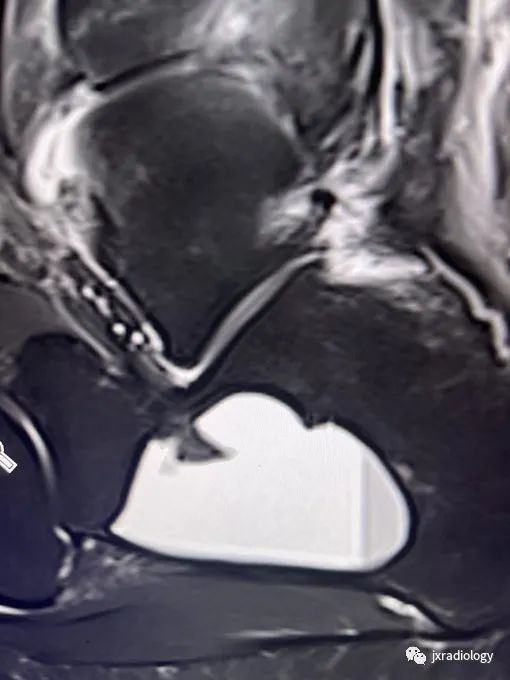

以下是踝关节磁共振显示的跟骨囊肿: